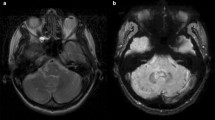

Correlation between T1-intensity and echo-intensity

TCS images of all 21 patients studied were qualified by the image analysis software to be of adequate quality allowing for the digitized quantification of DN and GPi echo-intensity. No correlation was observed between DPSIR or GTSIR and corresponding DN and GPi echo-intensity measures (each, p > 0.14; Fig. 2a, b).

Diagrams showing the relationship between T1-intensity and echo-intensity on digitized analysis of exact real-time MRI-ultrasound fusion images. Note that no correlation between T1-intensity and echo-intensity measures was found. a Relationship between dentate-nucleus T1-intensity (bilateral mean DPSIR on last MRI) and echo-intensity. b Relationship between globus pallidus internus (GPi) T1-intensity (bilateral mean GTSIR on last MRI) and echo-intensity